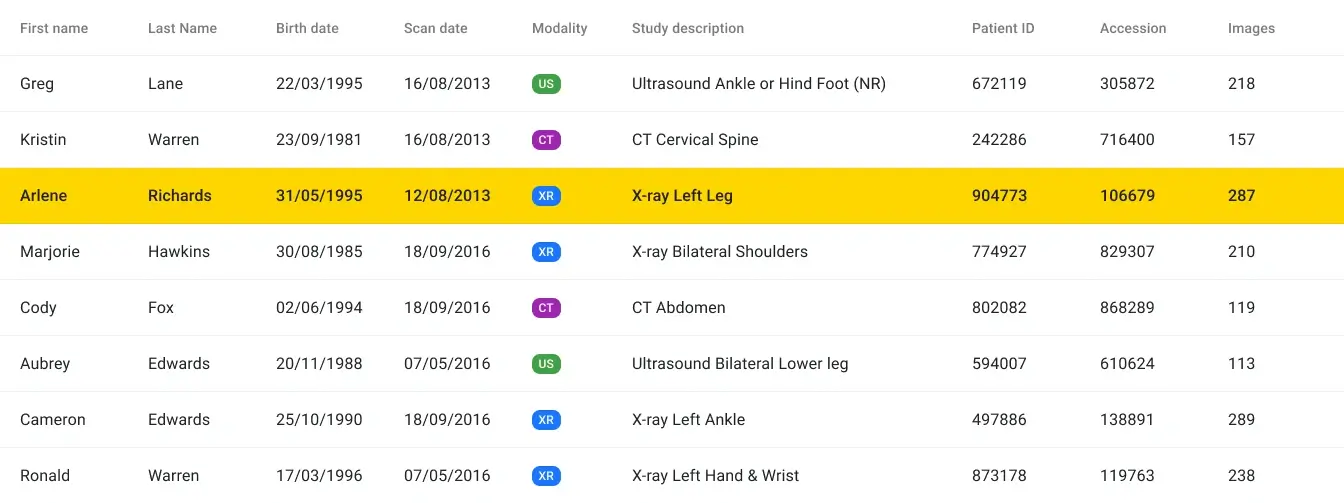

Report viewing

Enable referrers or specialists to access patient reports directly, eliminating the need for additional communication with your clinic.

Specialists access

Break-glass access for specialists

Provide your specialists with a break-glass access option, allowing them a single login to access all your patient data when necessary.